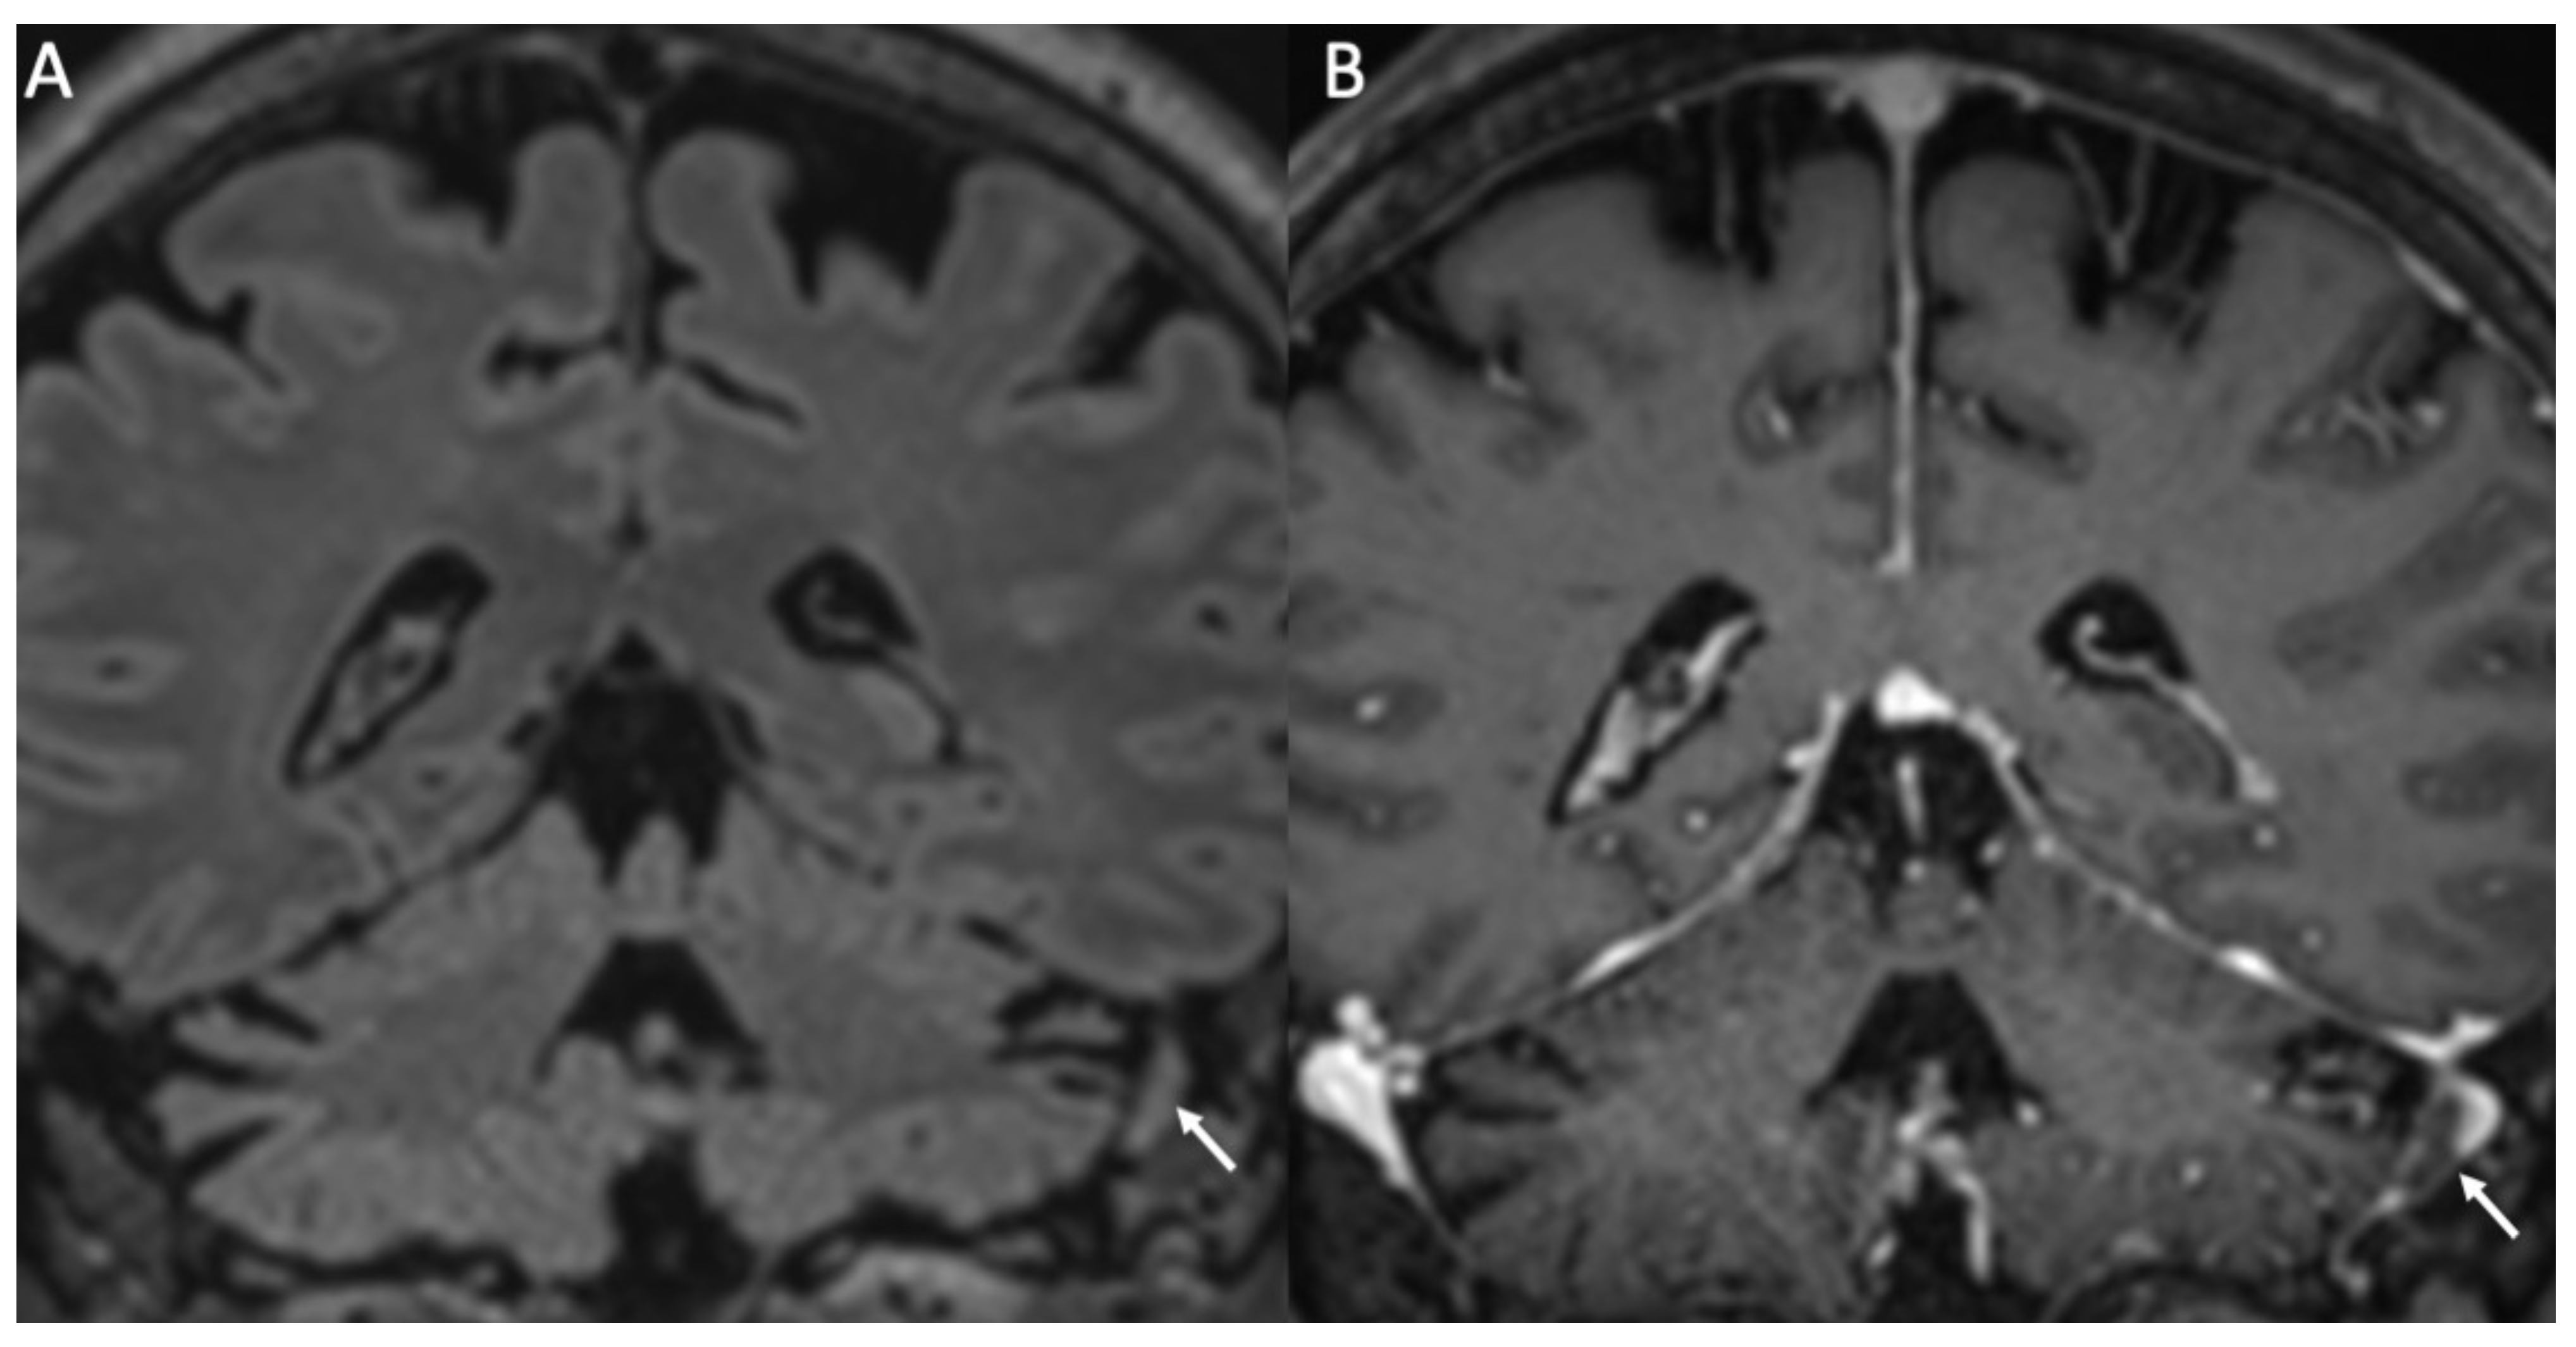

| Piogenic Meningitis | • Cerebrospinal fluid hyperintensity in T1 and FLAIR • Restricted diffusion of the subarachnoid spaces • Meningeal enhancement on T1 and FLAIR |

| Cryptococcus Neoformans | • Leptomeningeal enhancement • Cryptococcoma • Gelatinous pseudocysts |